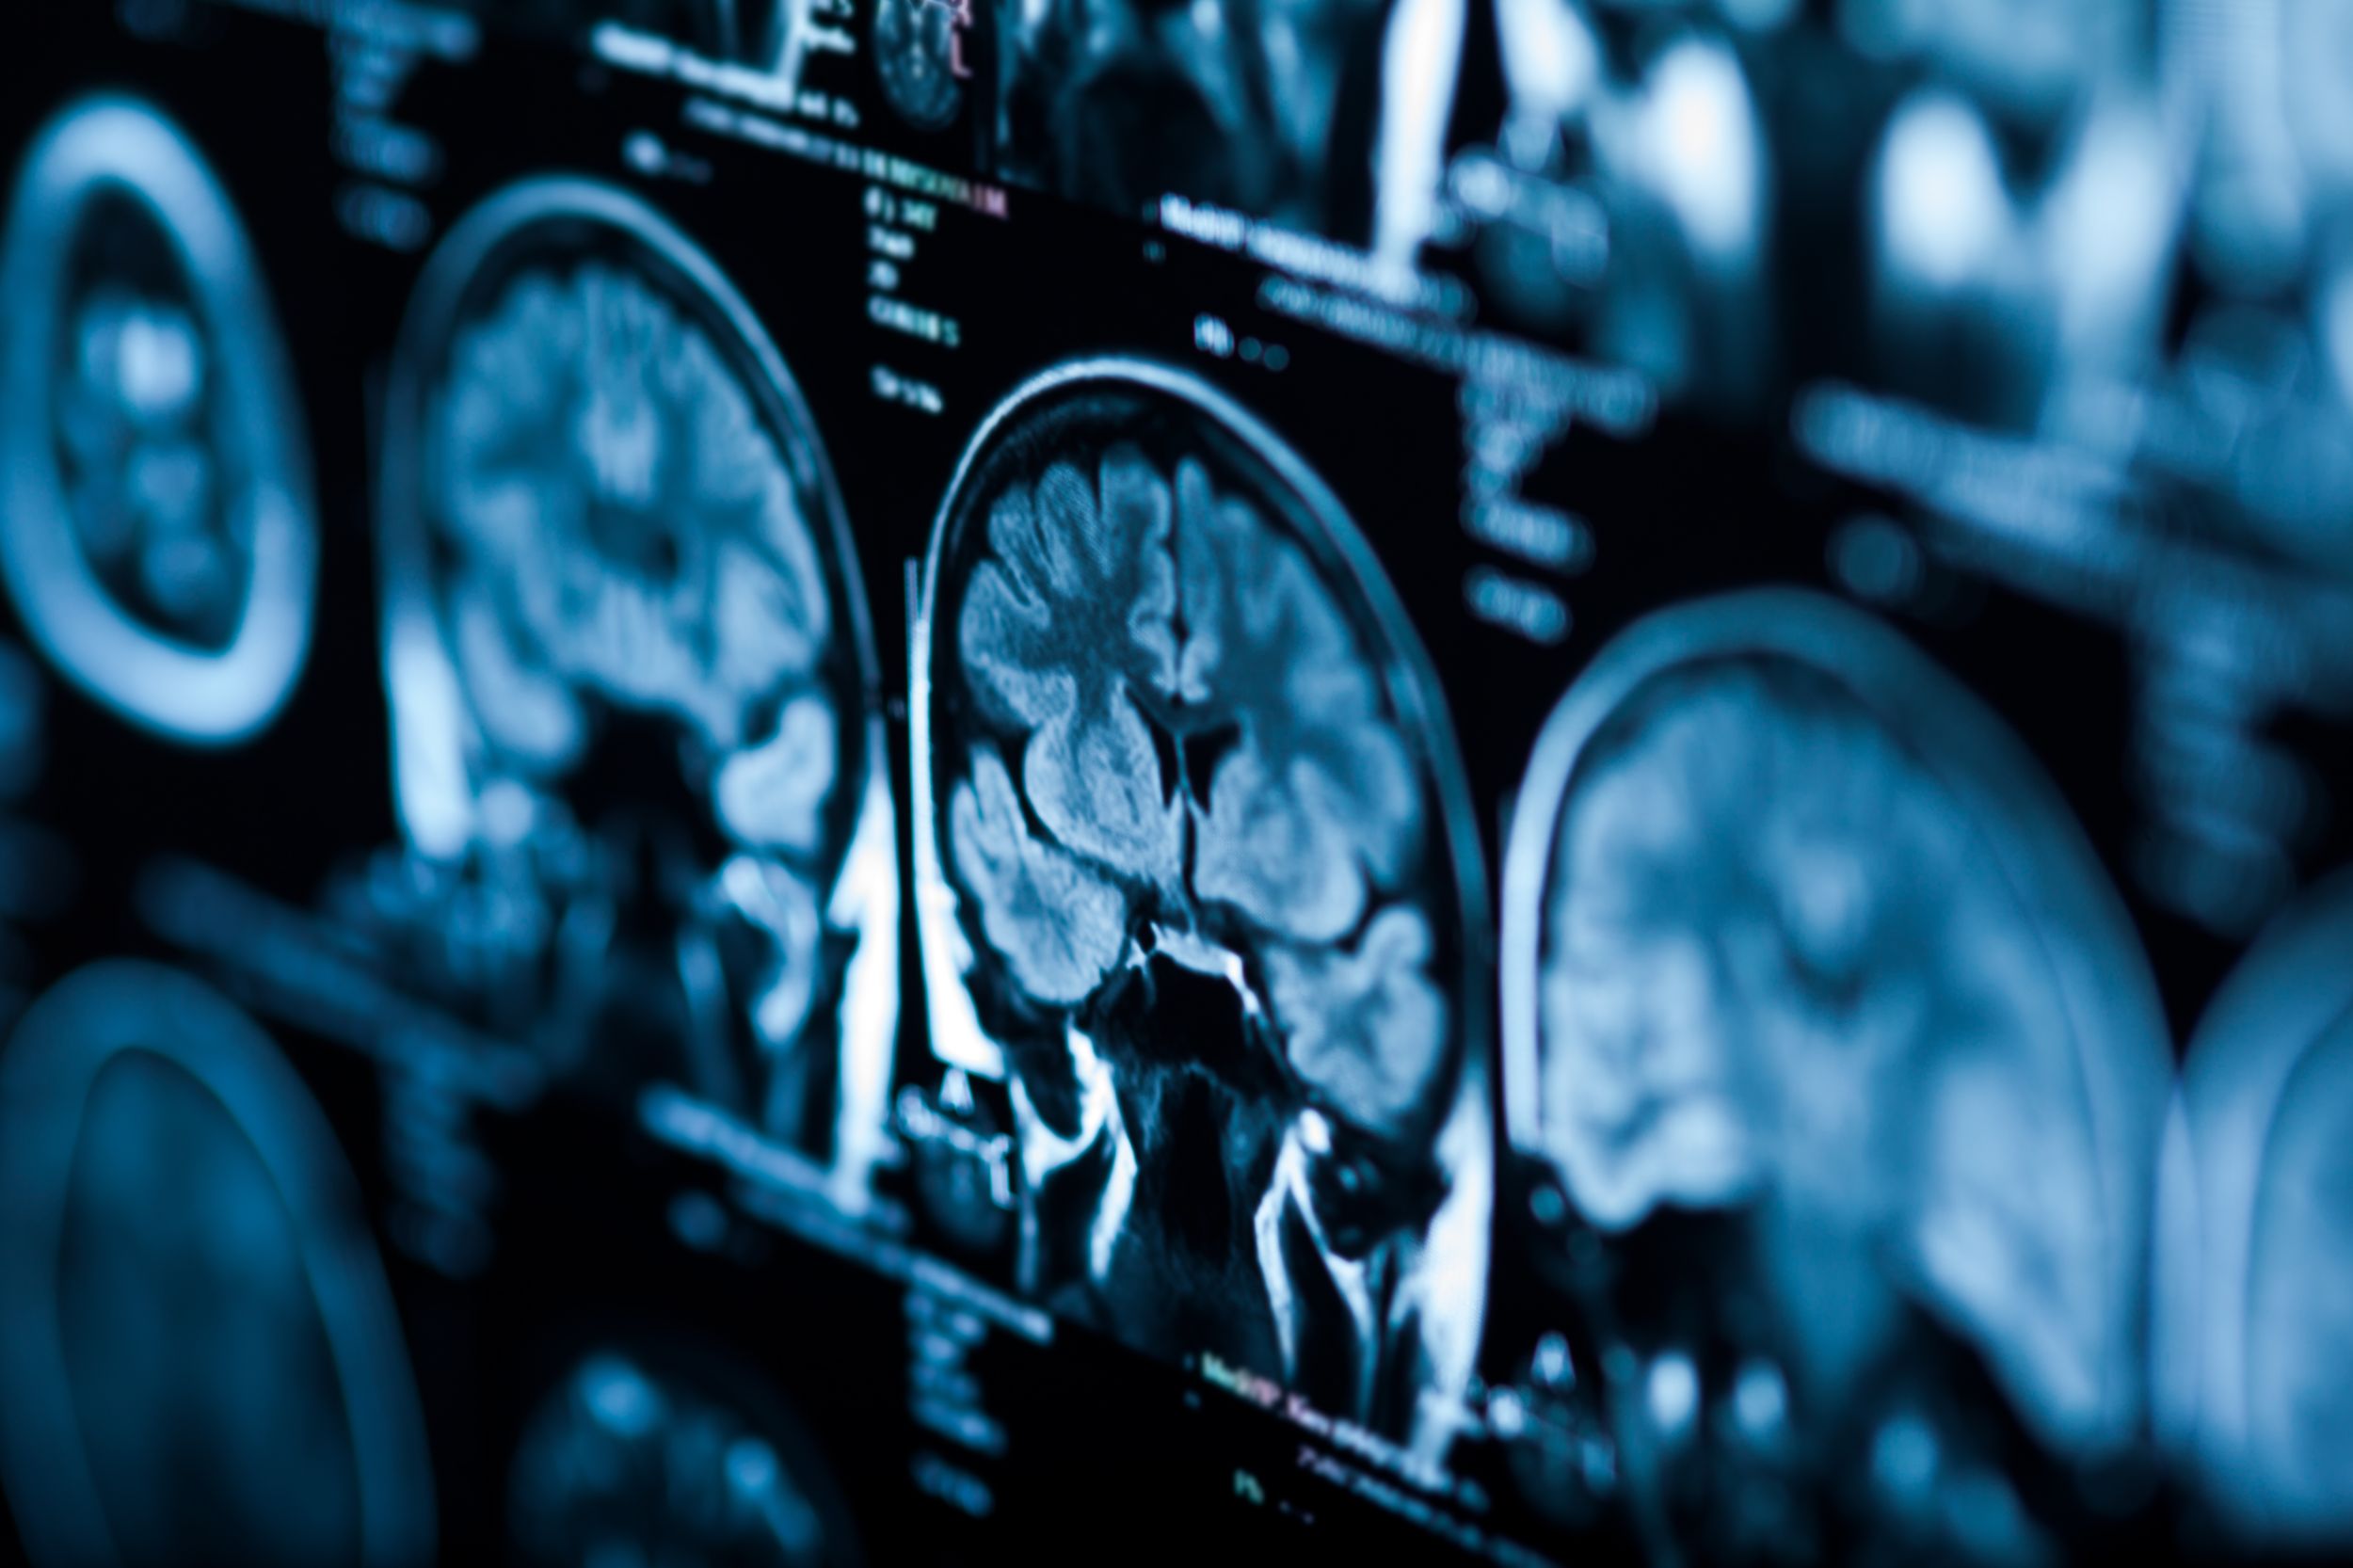

Diagnostic

L'examen le plus important est l'imagerie par résonance magnétique (IRM). En complément, d'autres techniques d'imagerie et des examens tissulaires (biopsies) peuvent être nécessaires pour planifier au mieux la thérapie.